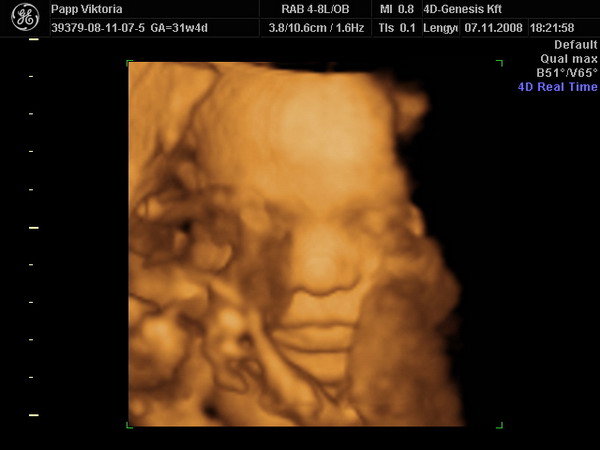

Hoztam VALAKIT:

Nem volt egyszerű, belebújt a drága a lepénybe a pofijával és fölénk mutatta az egyik ujját (lehet a középsőt?! :lol: :lol: :lol: ) de végül azért láttunk valamennyit belőle!

Minden OK, 1800 g, 3600 körül lesz a 40. hétre. Engem is megnézett a néni, lepény 0 fokban érett, keringés, stb minden rendben! Láttuk a kis golyóit is, már leszálltak a zacsiba. Nyitogatta a szemét, száját.

Képzeljétek, láttak egy mellső fali lepényt is :shock: , Levente ezerrel cuppogott rajta...állítólag nem gáz, csak szülésnél figyelni kell majd rá, hogy kijöjjön. Eddig kb 15 uhun voltam és sosem látták... :roll:

A lényeg: nagyon boldogok és büszkék vagyunk a Kisfiunkra!!!!!!!!!!!!!!!!!!!!!!!! :lol: :lol: :lol: